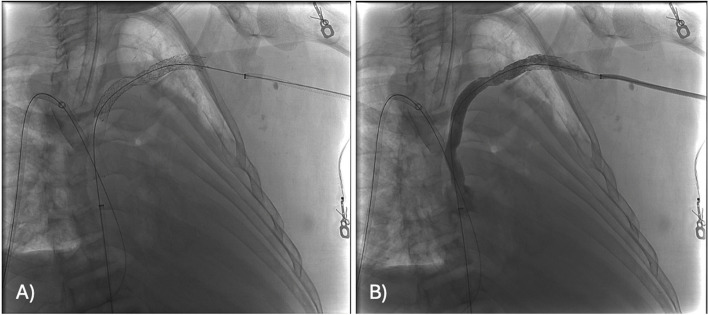

Axillo-caval extra-anatomic venous bypass creation via direct percutaneous puncture of the superior vena cava.

Abstract Image